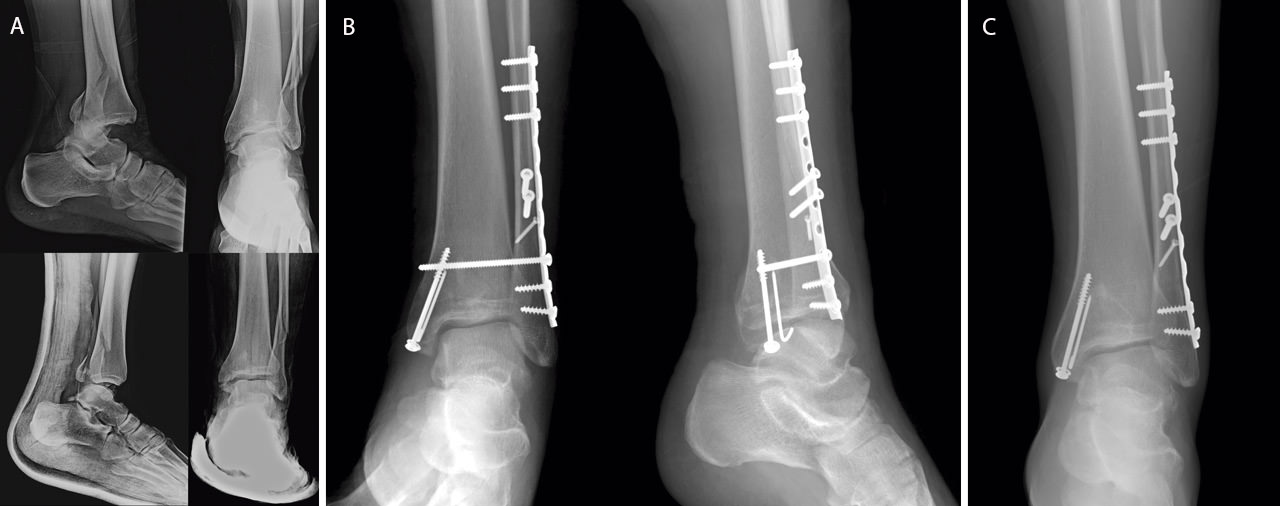

• El hook test, que se muestra superior al test de rotación externa. El hook test consiste en traccionar del peroné en sentido posteroexterno con ayuda de un gancho. Se considera positivo en caso de traslación superior a 2 mm. En esta situación está indicada la fijación con un tornillo transindesmal(3)(14)(31)(Figura 4).

Figura 4. Varón de 26 años con fractura-luxación de tobillo tras sufrir accidente de moto (A); reducción abierta y fijación interna. Se realiza fijación con tornillo transindesmal tras comprobación intraoperatoria de inestabilidad sindesmal (B); retirada de tornillo trasnsindesmal a los 4 meses (C).